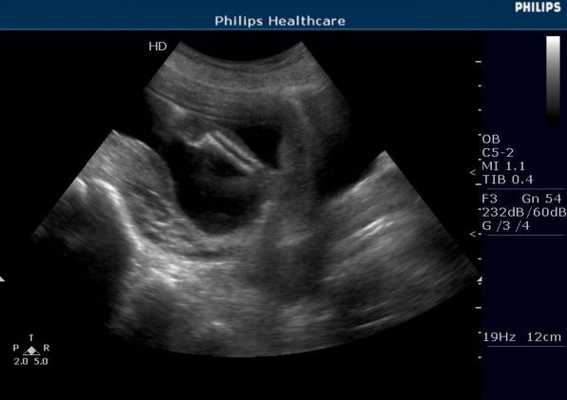

УЗИ в акушерстве и гинекологии

Акушерство. Приоритетное использование метода в акушерстве связано с отсутствием ионизирующего излучения и возможностью поэтому динамического наблюдения за пациентом. Техническая простота также относится к преимуществам УЗИ. Важной оценкой эффективности данной диагностики является снижение заболеваний и смертности матери и плода, что может быть достигнуто за счет более точного определения срока беременности и родов, выявления аномалий развития плода и многоплодия. Особое место занимает ранняя диагностика внематочной беременности.